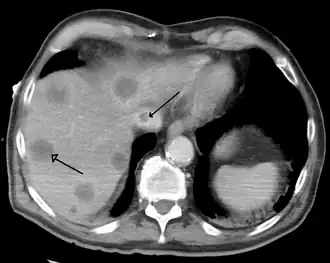

| A gross pathology specimen of liver metastases caused by pancreatic cancer | |

A previously undiagnosed liver disease may become evident first after autopsy. Following are gross pathology images: